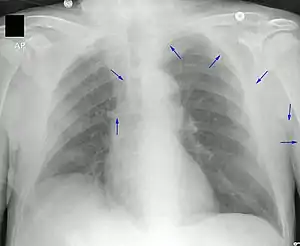

A PICC is inserted in a peripheral vein such as the cephalic vein, basilic vein or brachial vein in the arm, and then threaded through the veins toward the heart, until the end of the catheter rests in the proximal superior vena cava or cavoatrial junction. They must be inserted by a trained medical professional, including a physician, but also any trained medical professional such as a specially trained registered nurse.[5] An ultrasound or chest X-ray, or the use of fluoroscopy, can be used during insertion and to confirm placement. The insertion is a sterile procedure, but does not need to be performed in a completely sterile environment like an operating room.

First described in 1975,[1] it is an alternative to central venous catheters in major veins such as the subclavian vein, the internal jugular vein or the femoral vein. Subclavian and jugular line placements may result in pneumothorax (air in the pleural space of lung), while PICC lines have no such issue because of the method of placement.